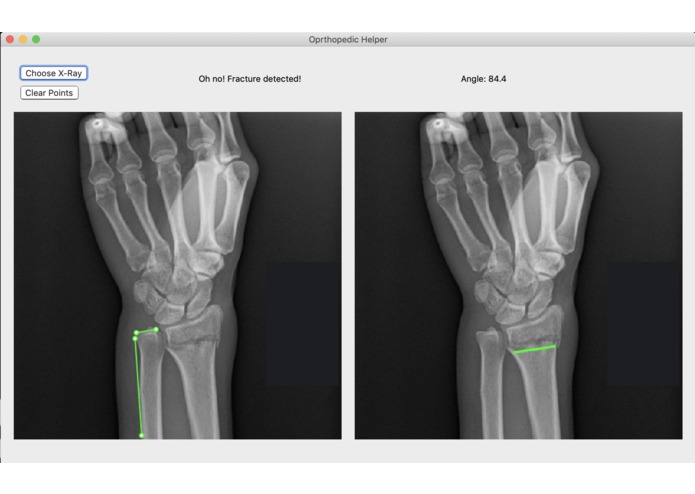

Broke Detector is a simple tool to help analyze the site of wrist injury. It helps doctors decide a) whether the bones are broken or not (which is admittedly very simple for humans, but not for computers) and b) provides tools such as a protractor to provide an objective measurement of how misaligned bones are. Broke Detector aims not to replace the orthopedist, but to aid them.

The actual detection algorithm is the guts of this project (no machine learning involved). The process is as follows: Thresholding: Reasons for this will be listed in the next section, we did this using color histograms to determine the percentile of certain pixel values. Edge detection: We used a simple Söbel kernel (however, not the default opencv one) to handle edge detection, as it was simple to detect only horizontal edges. Hough transform: This is the guts of the algorithm, which decides where horizontal lines are in the X-Ray. It sounds dumb, but choosing the lowest isolated horizontal line almost always results in finding the break in the bone. Flask: We developed a locally hosted web application which supports uploading from the computer. The HTML formatted site displays the results of the Python calculations.

Another challenge with this project was that the GUI framework we went with, wxPython is not only slow but antiquated in terms of GUI design. Something as simple as drawing lines on an image proved to be an immense challenge of trudging through documentation to find the obscure function call that enables something that should be the default anyway.